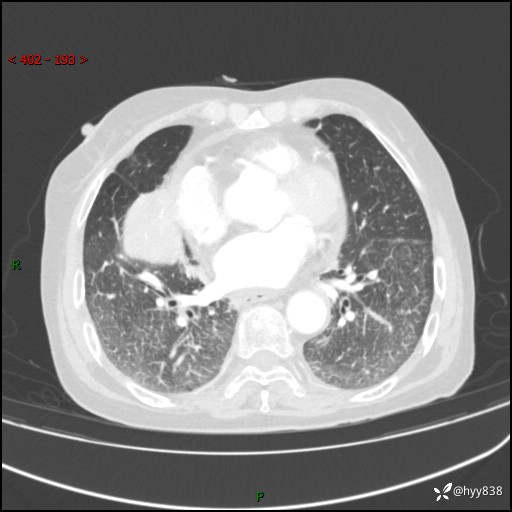

胸部CT增强(外院平扫)